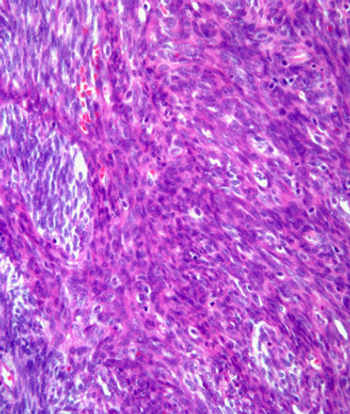

This slide show features a CT image, and pathology images of gastrointestinal stromal tumors (GISTs) arising in the stomach using H&E, CD34, and c-Kit staining.